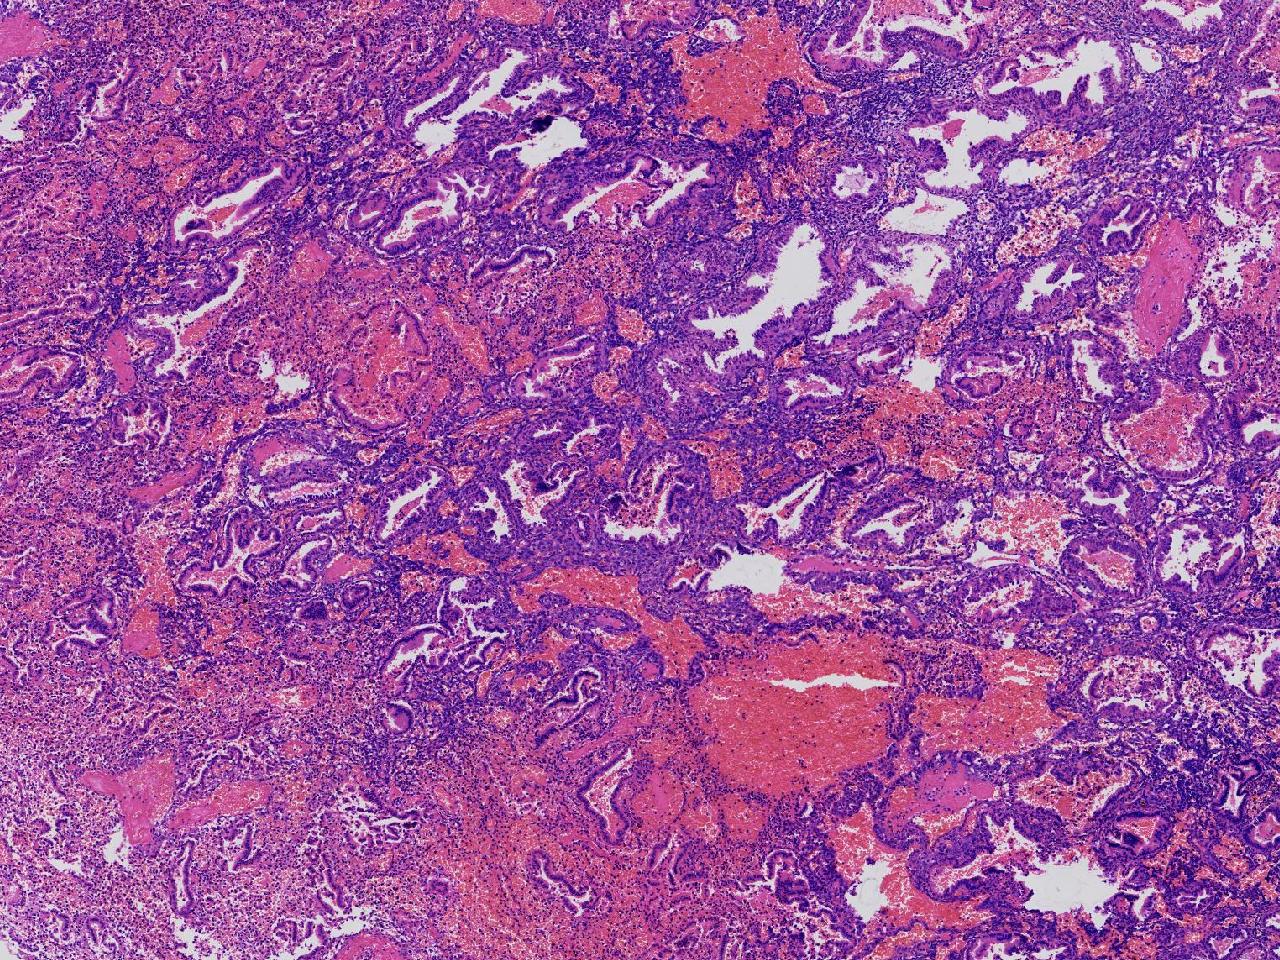

性别

女

年龄

45岁

临床诊断

阴道不规则出血20余天,

一般病史

彩超示:宫腔内见约41X11毫米的不均质回声区。宫腔镜示:宫腔形态正常,内膜粉红,不规则增厚。

标本名称

子宫内膜

大体所见

灰粉色不整形软组织多块,1.5X1X0.6厘米。

分泌反应子宫内膜,伴有出血。

晚泌期及月经早期改变,局部呈啫酸性乳头状化生改变。